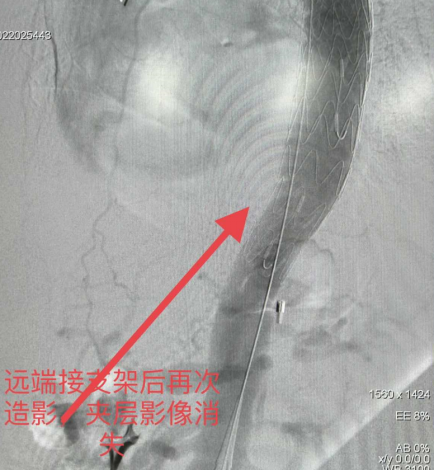

医学影像检查结果面前,患者王大娘的家人立刻理解了病情的凶险程度,同意血管外科团队的治疗方案。经过将近1个半小时的术前准备,10月22日凌晨2点50分,“胸主动脉夹层腔风隔绝术”正式开始。这是济南市中心医院东院启用以来的首例B型夹层手术。

非常凶险的B型主动脉夹层,2小时30分钟完成手术,说明了什么?

济南市中心医院血管外科副主任医师刘兆轩介绍说:“患者术前诊断明确,患者家人非常支持医生的急诊手术方案,另一方面是手术方式是微创介入,一切操作都是导管操作完成,几乎没有创伤。更重要的一点是东院胸痛中心的急诊急救流程设置得非常科学,各项检查均集中在一层楼内,非常方便,为术前准备节约了大量时间。也可以这么理解,从发病到展开手术的时间越短,手术时机就越靠前,手术过程就相对顺利。患者在急救过程中的每一步流程,都离不开患者家人的信任与支持,所以患者的手术顺利是医患者双方齐心协心的结果。”